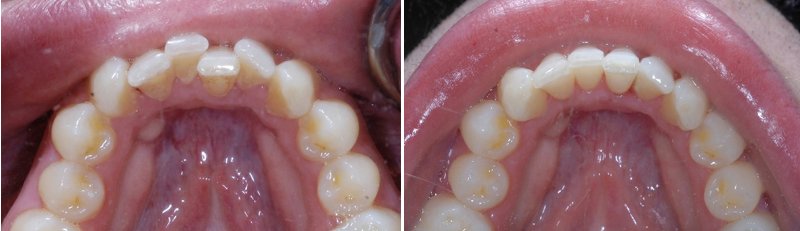

儿童牙齿矫正前后对比